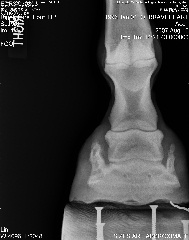

Posted on Friday, Aug 10, 2007 - 6:54 pm: We can trot on straight lines! Vet said he's at the limit from the coffin bone to the wall, that's not good, but he said he thought his angles looked ok. He thought that since the fetlock joints were off, he'd need more wall on the ;left front inside and more wall on the right front on the outside, then that should fix that. He said he'd like to see more sole, but he hooftested him and said his feet are rock hard so that should not be a worry for now. He's going to compare these to December's xrays and call. But based on what little he saw on the xrays and how he moved on the lunge, he said as long as I ride him in boots he should be just fine Here's a link to the xrays: https://s141.photobucket.com/albums/r59/wishes_album/xrays%20aug%2007/ Here are smaller versions: LF Lateral LF DP RF Lateral RF DP Edited to add that he was shocked that he could feel ribs when he asked Brave to move over But yes, he still is on a strict diet.

|

Posted on Friday, Aug 10, 2007 - 7:32 pm: Dr. O or anyone, Do his heels need to be lowered? I find it odd asking this question, but based on the xrays...Thanks! |

Posted on Friday, Aug 10, 2007 - 8:10 pm: Well, you can see from the laterals, his heels don't need to be higher. Are they back to the widest point of the frog? Breakover still looks too far forward to me if it's indicated by the white contrast line, but perhaps that's an illusion? |

Posted on Friday, Aug 10, 2007 - 9:27 pm: and this from the vet that was extremely resistant to your going barefoot? to the point that you were afraid he'd DrOp you if you did?...hmmmmmmm.....i think you're heading in the right direction with his feet..breakover still needs to come back a tad, as well as the heel.. remmeber that the widest part of the foot should be at about the halfway point... his is farther back than that... that makes the breakover too far forward.. but they look tougher than ever and am so glad you've been given the ok to ride some... congrats and have fun!!! |